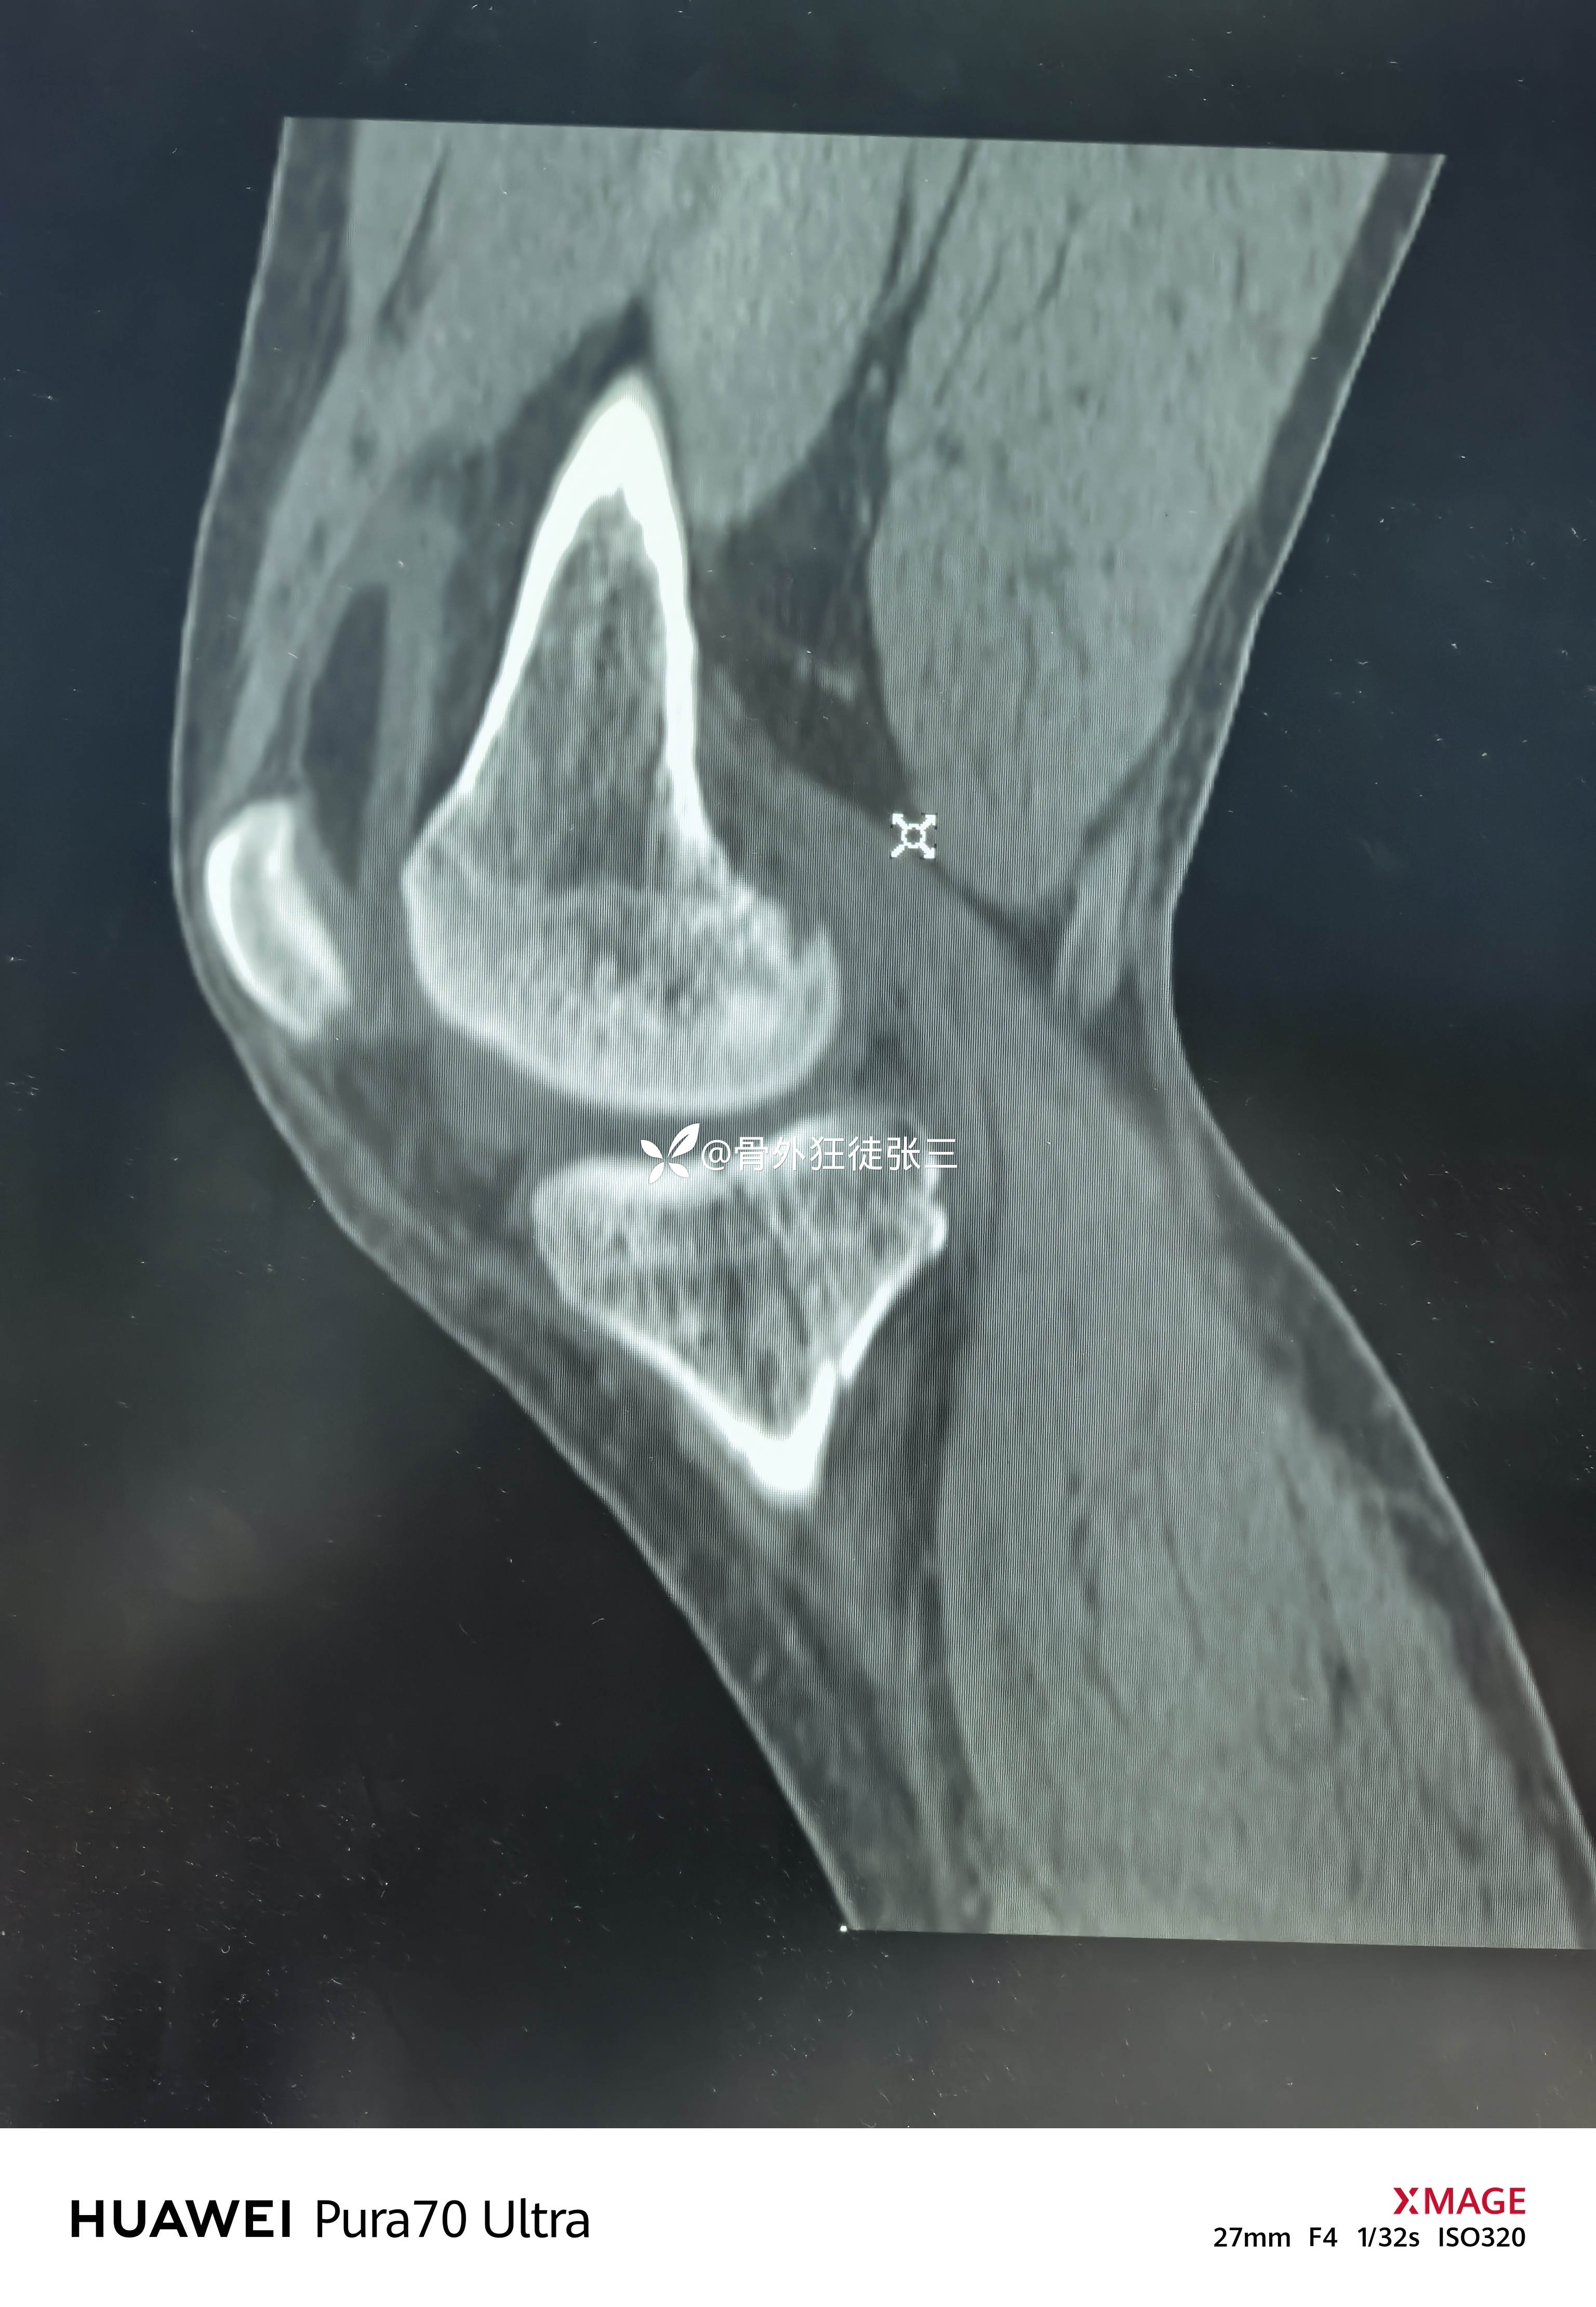

但是CT下显形惊涛骇浪

右胫骨平台骨折

(屈曲内翻型——后内侧平台骨折+外侧平台塌陷+ACL止点撕脱)